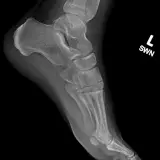

Over 2,100 interactive radiology cases, curated by radiologists for your level of training. Scroll, window, and view cases full screen — just like on PACS. Click linked findings in each writeup to jump straight to them on the image. Cases include sample reports, a focused discussion section, original illustrations, and videos.

PACSで期待されるツールを完備した完全インタラクティブな症例 — スクロール、ウィンドウ調整、ズーム、パン、計測、ROI、フルスクリーンモード。

重要な所見を症例画像上に直接ハイライトする豊富なアノテーション。症例解説内のリンクされた所見をクリックすると、スキャン上の正確な位置へジャンプできます。